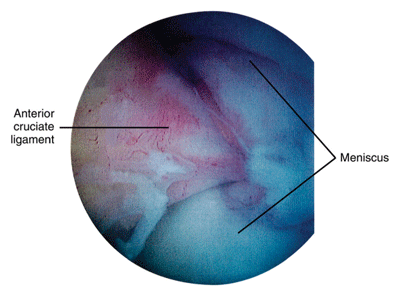

If you have osteoarthritis of the knee, you may have undergone or be considering arthroscopic lavage and debridement (see Figure 9 below). Osteoarthritis of the knee is often treated with arthroscopic lavage and debridement in an attempt to improve pain and function. In lavage, torn pieces of cartilage and other debris are washed out of the joint, and debridement involves smoothing of joint surfaces. Because of unpredictable outcomes, such surgery on the osteoarthritic knee is controversial. Evidence suggests that these procedures fail to provide pain relief in many cases. For example, patients with unstable meniscal cartilage tears are likely to improve after surgery, while patients with malalignment problems of the knee and severe OA of the medial compartment are not as likely to have good results.

Figure 9: Knee arthroscopy.